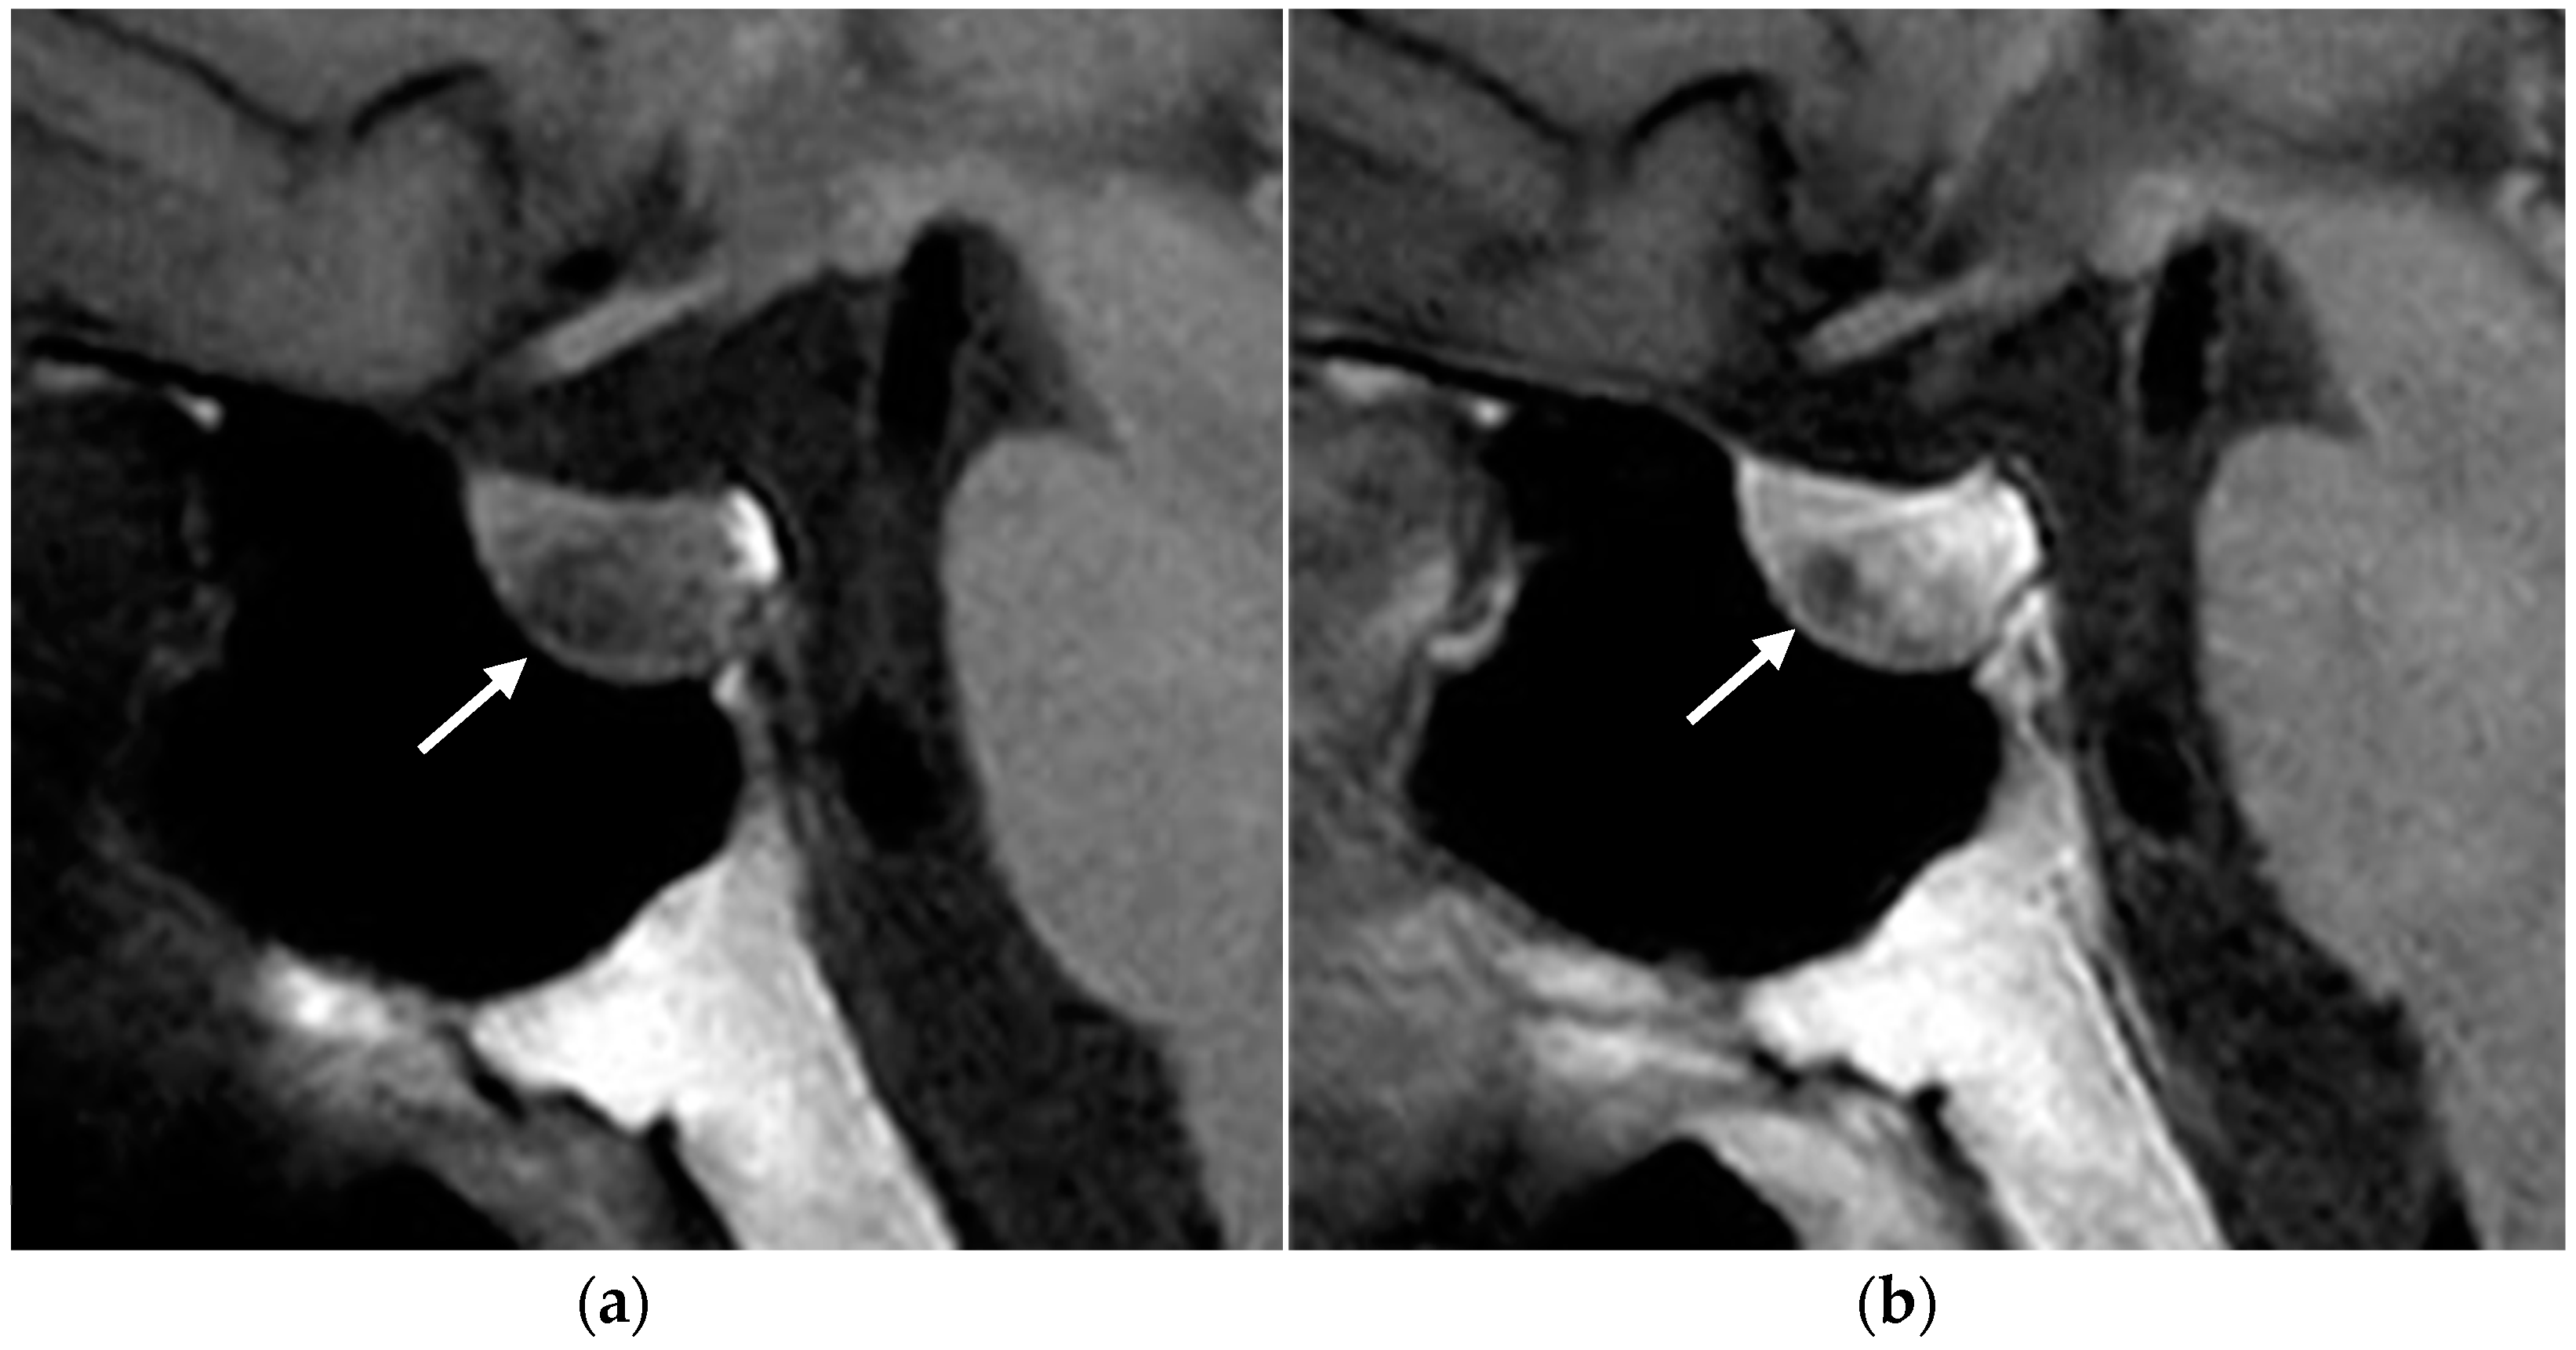

Adenomas are often isointense to the adjacent pituitary parenchyma in T1- and T2-weighted sequences. However, microadenomas can be slightly hyperintense on T2-weighted images and have a delayed enhancement compared to the background pituitary parenchyma (Figure 8). Some small microadenomas are not always visualized on imaging, and therefore it is important to acquire dynamic post-contrast sequences, as they increase the sensitivity in identifying the lesion, and to look for secondary signs, such as erosion of the sellar floor or focal convexity of the superior pituitary gland [17].

Figure 8.

Pituitary micro-prolactinoma. T1-weighted MR images before (a) and after (b) contrast administration showing a hypointense and low-enhancing nodule (arrow) in the anterior pituitary gland.